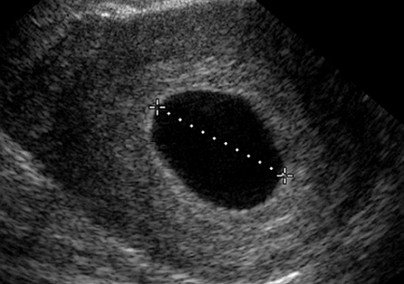

hasil USG BO

hasil USG BO

kantung kehamilan kosong

kantung kehamilan kosong